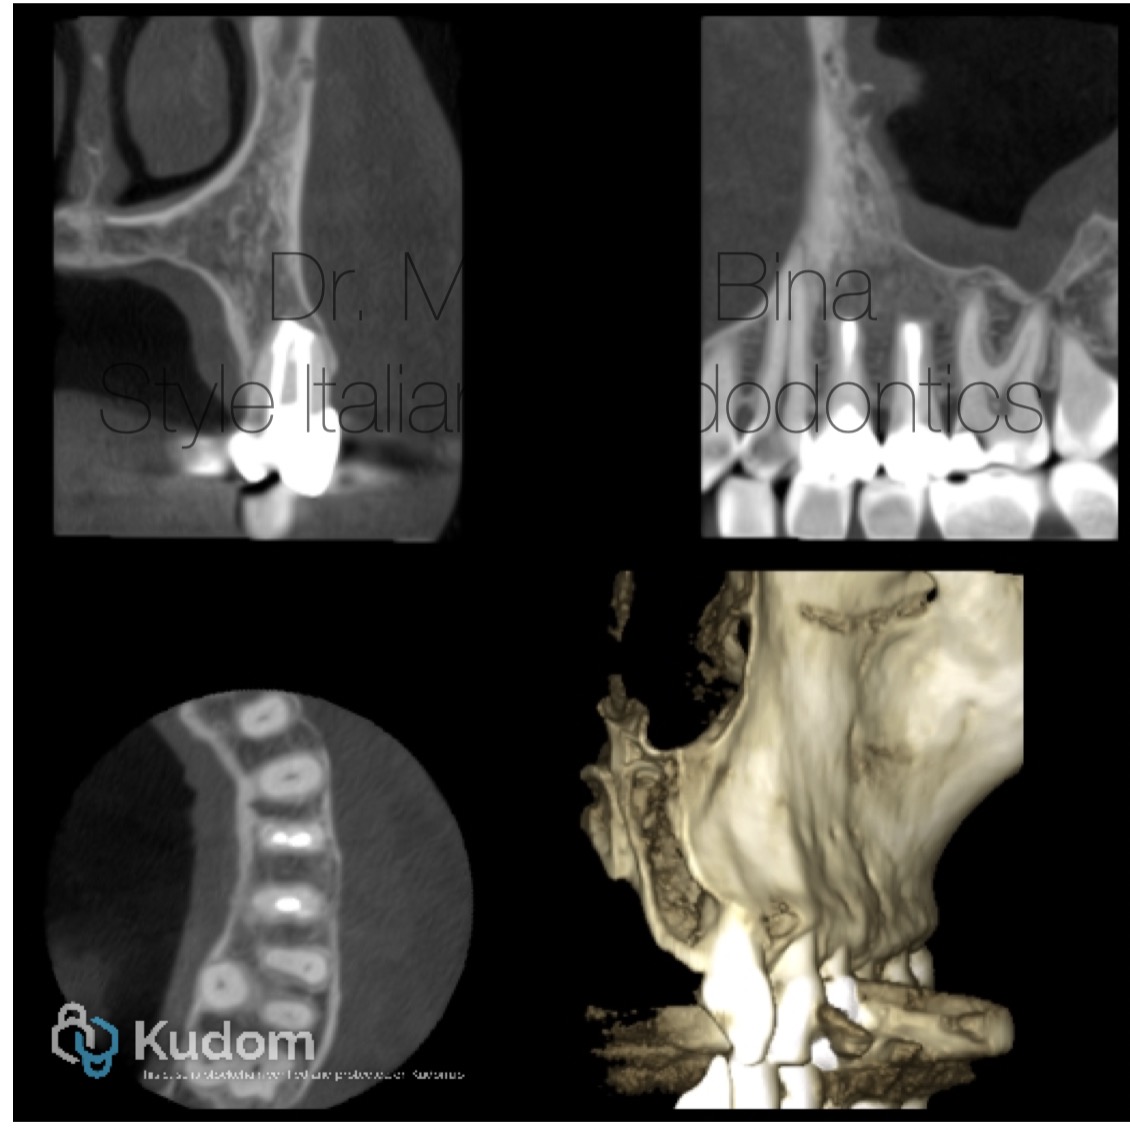

Fig. 5

Post operative CBCT with complete healing